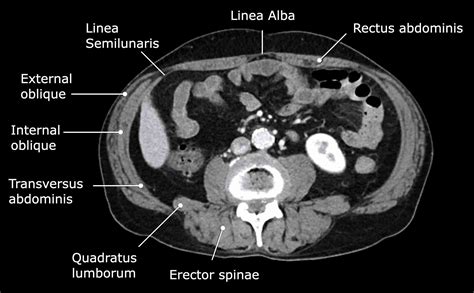

The Radiology Assistant : Abdominal wall hernias

Discover the latest advancements in surgery for an abdominal wall hernia. Our expert guide covers effective treatment options, minimally invasive repair techniques, and essential recovery tips. Learn how to manage ventral and incisional hernias, reduce complication risks, and improve your surgical outcomes with evidence-based medical care designed for long-term health and patient comfort.